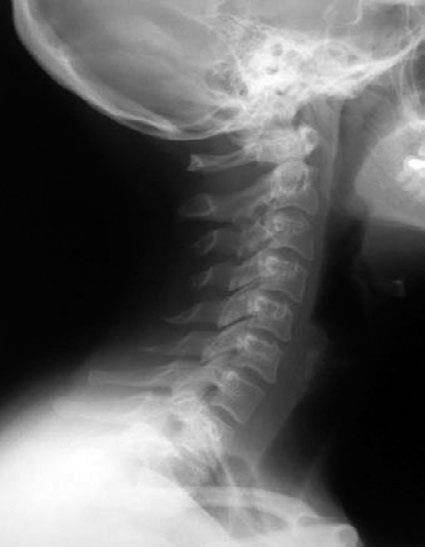

Рис. 1. Нормальная статика шеи.

Правильный физиологический изгиб: A = A1